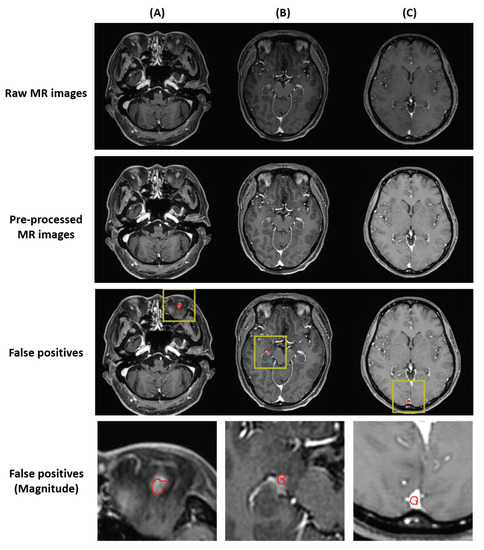

The locations of false positives can be summarized in three ways (Figure 4). First, the false positives were found outside the brain structure. Second, the false positives were found in a structure with high intensity. Third, the false positives were found in the superior sagittal sinus.

Figure 4. Locations of the false positives. (A) Delineation created outside the brain; can be solved with skull-stripping. (B) Delineation created in a structure with high intensity; can be solved with extensive gamma correction. (C) Delineation created in the superior sagittal sinus; can be solved with black-blood sequencing. In each images, red in the yellow bounding box indicates false positives.